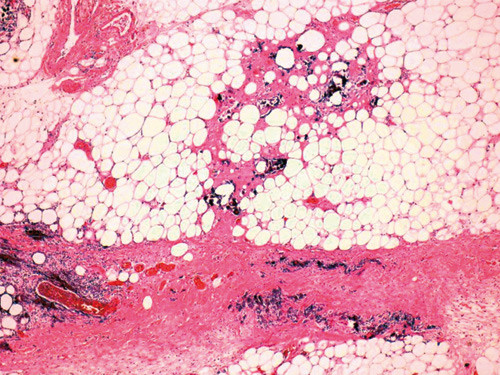

Det ble tatt hudbiopsier til histologisk undersøkelse, og mikroskopi viste hud og subkutant vev med utstrakte kalsifikasjoner både i blodkar og i interstitielt vev. Warfarinrelaterte hudnekroser kunne utelukkes siden pasienten ikke benyttet preparatet. Siden kalsifikasjonene ble funnet også i karvegger (fig 2), ble dette vurdert som sannsynlig kalsifylaksi på bakgrunn av kronisk nyresvikt og sekundær hyperparatyreoidisme.

Kalsifylaksi ses hovedsakelig hos pasienter med kronisk nyresvikt og sekundær hyperparatyreoidisme. Tilstanden er assosiert med feilernæring, overvekt og diabetes. Som regel manifesterer den seg som smertefull, iskemisk kutan nekrose på underekstremiteter eller abdomen. Små og middels store blodkar affiseres, og mikroskopisk ser man forkalkninger både interstitielt og i karvegger. Dette fører til iskemi med påfølgende ulcerasjoner og nekroser i hud og subkutant vev.

Ved obduksjonen fant man på høyre mamma et nekrotisk hudsår på 10 x 10 cm. Under overflaten var det fast infiltrasjon i subkutant vev. På nedre del av abdomen var det et tilsvarende sårområde med store nekroser som målte totalt 20 x 30 cm (fig 3). Det var normale forhold i kroppshuler, hjerne, lunger og fordøyelseskanal. Hjertet var moderat forstørret med vekt 660 g og med betydelig aterosklerose i koronararteriene, men ellers upåfallende forhold. Begge nyrene var små. Den venstre veide 140 g og den høyre 175 g. Det var tallrike små cyster i begge nyrene, og barkhøyden i nyreparenkymet var tydelig redusert. Mikroskopi av nyrevev viste segmental og global sklerose av glomeruli, og cystisk dilaterte tubuli. Der var interstitiell fibrose og betydelige kalkavleiringer. Parathyreoideakjertlene var moderat forstørret, likeledes venstre binyre. Mikroskopi av de ulcererte og forkalkede områdene fra abdomen viste nekrotisk materiale, granulasjonsvev og betydelige forkalkninger både i blodkar og interstitielt (fig 4). Funnene var forenlige med kalsifylaksi. Det ble ikke påvist noe annet mulig utgangspunkt for hennes sepsis enn disse hudsårene.

Mikroskopisk ser man ved kalsifylaksi forkalkninger både interstitielt og i karvegger, sammen med ulcerasjoner og nekroser i huden og det subkutane vevet. Histologisk påvisning av kalknedslag i karvegger kan være nødvendig for å skille tilstanden fra arteriosklerotisk perifer karsykdom. Kalsifylaksi ble først beskrevet av ungareren Hans Selye i 1962, ut fra eksperimenter med dyr (1). En grundig beskrivelse av kalsifylaksi hos mennesker ble gitt av Gipstein og medarbeidere i 1976 (2). Benevnelsen kalsifiserende uremisk arteriolopati er foreslått for å tilkjennegi at kalkavleiringer i veggene på arterioler og arterier er av sentral betydning ved tilstanden (3). Kalkavleiringene ses hovedsakelig i veggene av arterioler og små og mellomstore arterier. Alle organer kan affiseres, men hud og skjelettmuskulatur angripes hyppigst. Karforandringene leder til iskemisk nekrose av det involverte vevet.